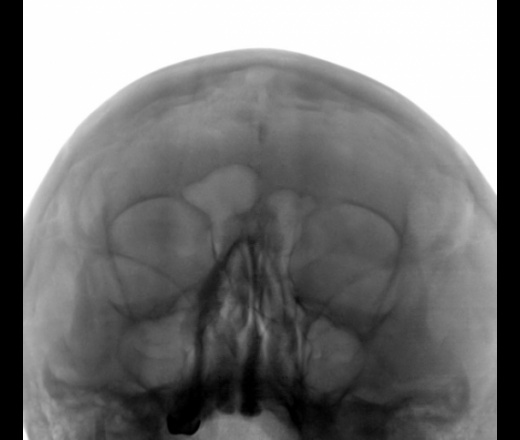

Пазухи не изменены, какое-то утолщение мягких тканей справа.

А чего ЛОР жаждал? Или у Вас в ЛПУ тоже в моде направительный диагоноз "Обследование"? Пазухи не зацепили. Вижу признаки гиперостоза лобной кости и ограниченное уплотнение серпа.

А что с медиальной стенкой правой гайморовой пазухи?

В лобной пазухе, то не остеома?

Имею в виду именно "это".